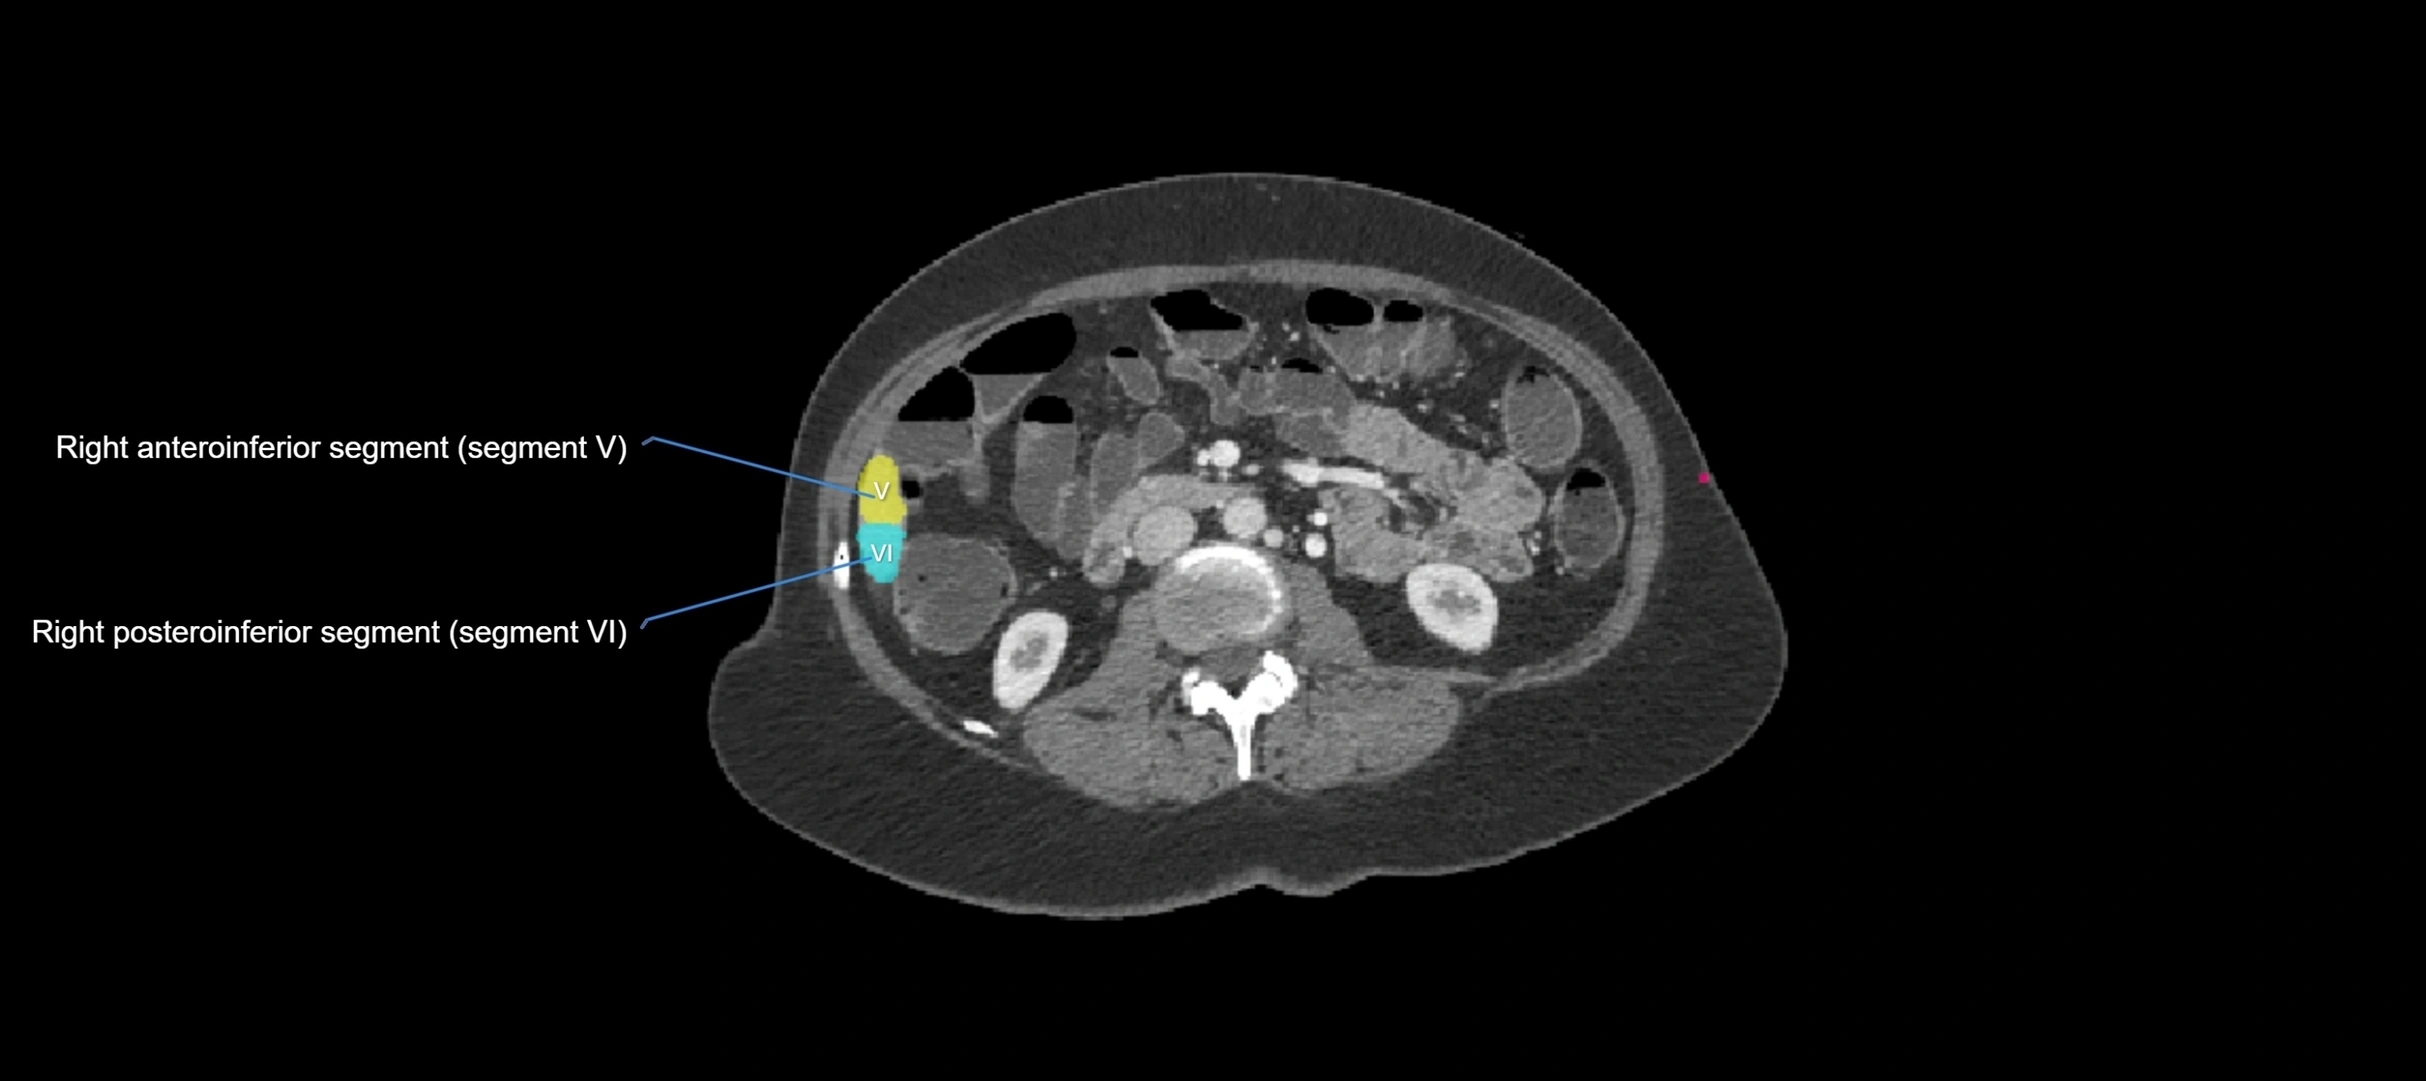

CT Image

image